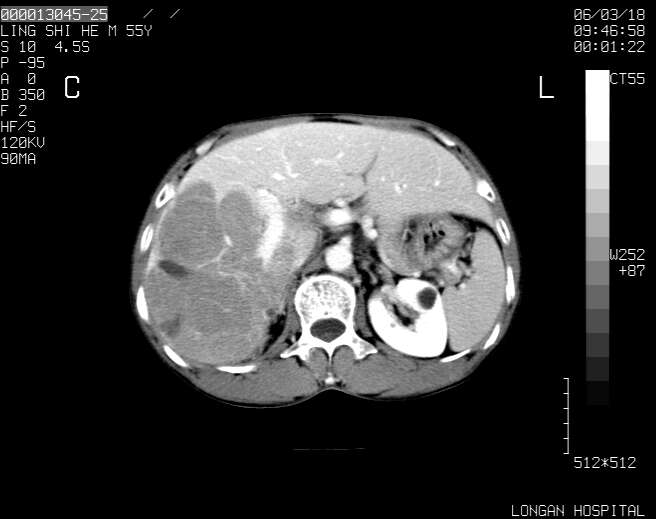

以下是引用guzhongliangddd在2006-3-21 22:13:00的发言:[br]病灶主要位于肝右叶的后份,内见异常血管,门脉主干及右支受侵{提示有癌栓形成},门腔间隙内见增大淋巴结。肝左叶内未见异常。

以下是引用zhuxinli在2006-3-22 1:23:00的发言:[br][br] 病灶主要位于肝右叶的后份,内见异常血管 .门脉右支截断,右叶前段早期强化(考虑动静脉漏),腹膜后肿大淋巴结,病灶逐渐强化,考虑为胆管细胞癌[br]